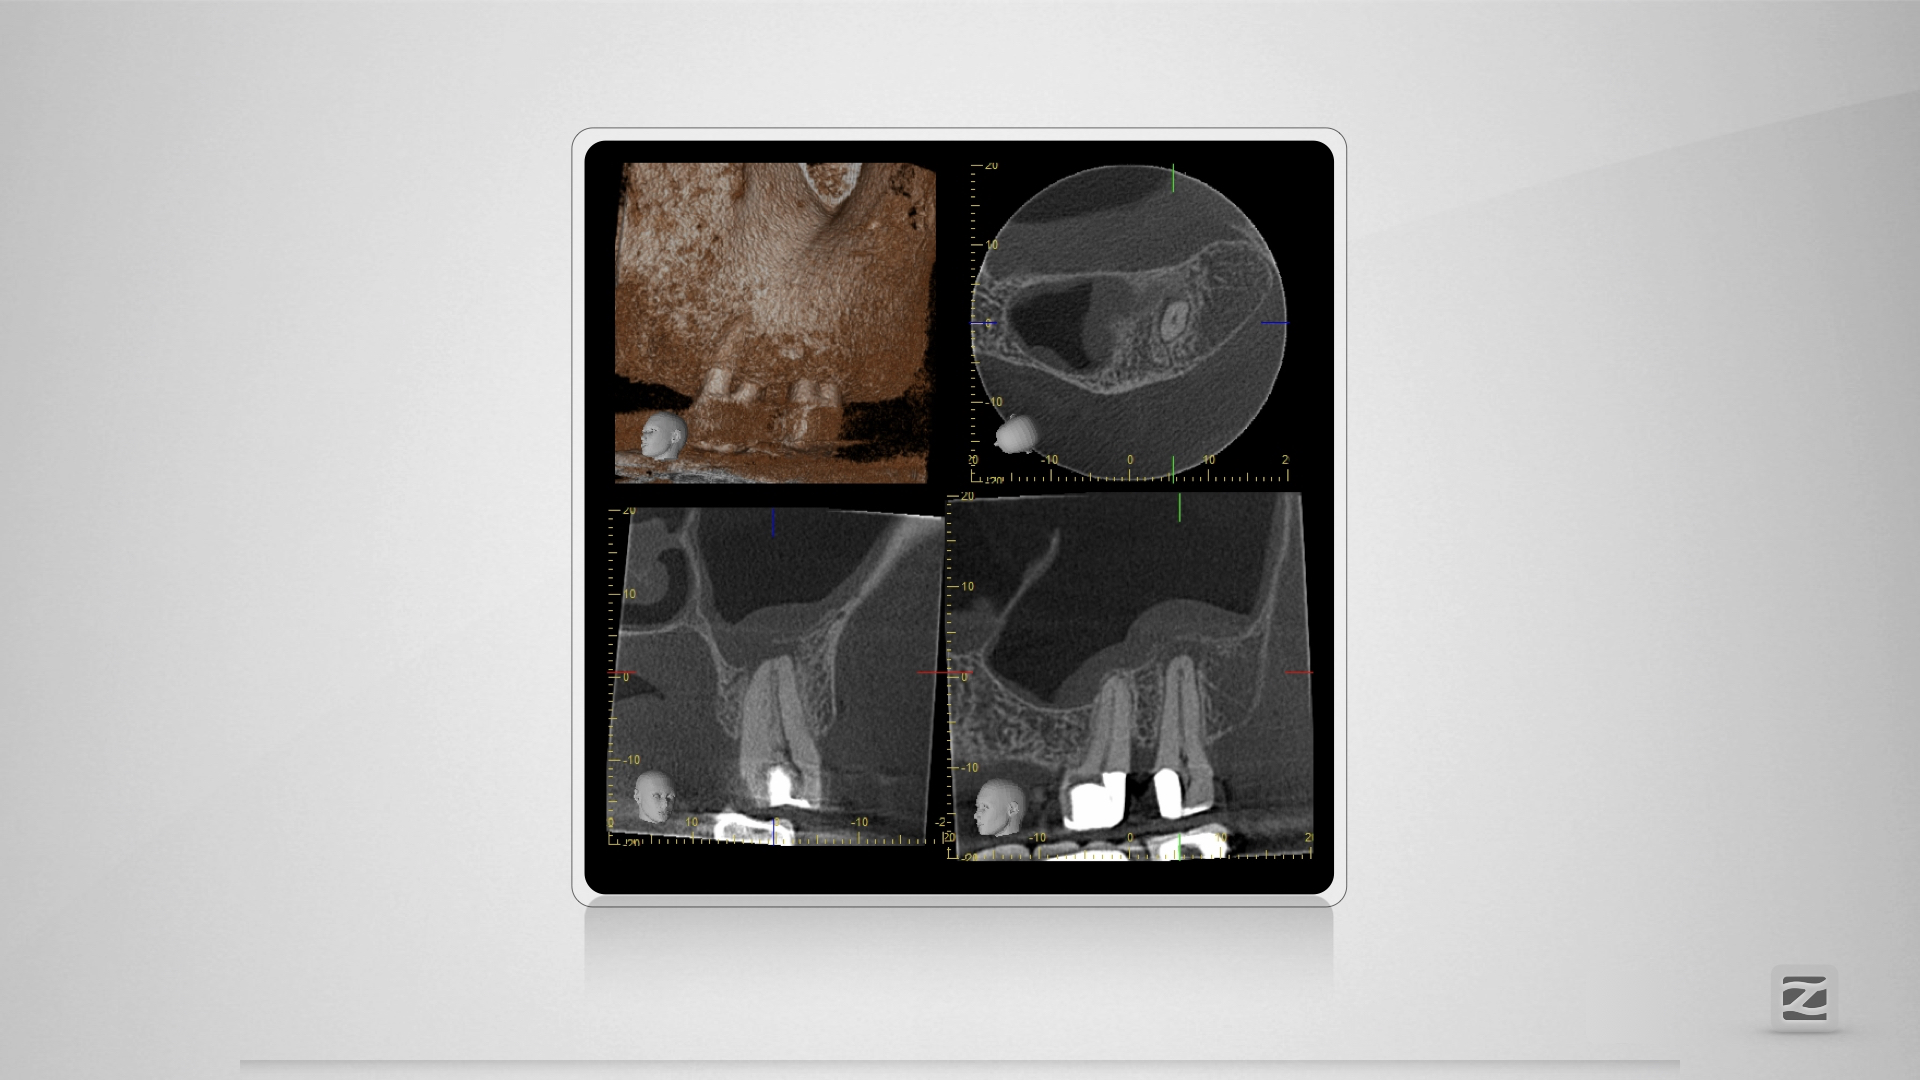

27D.006

Großer Dentikel, tiefer Split.